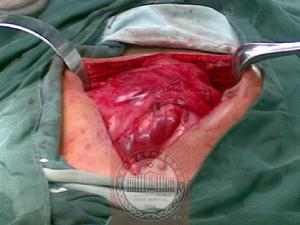

腹繭症 包膜切除後

腹繭症 術中所見併發症

1.11 有症狀型 多以急性或慢性腸梗阻就診,包膜的下面有腸管的縮窄環,應以手術為主,徹底切除包膜、充分松解粘連及縮窄環,應以手術為主,徹底切除包膜、充分松解粘連及縮窄環,解決腸梗阻問題。5例患者中有1例全腹臟器包裹成團,似水腫的腸系膜,無法辨認腸管,纖維膜異常肥厚,約30mm,緻密堅韌,只能用小圓刀慢慢切開,將其松解,但腸管、系膜間的粘連分離起來還較容易,我們的經驗是打開一側的側腹膜,游離結腸,將整個“盤狀物”翹起,在系膜、腸管間分離直至表面的纖維膜並切除之,這樣由易到難的操作可最大限度地避免損傷腸管,也能節省時間,以免在表面無處下手而浪費時間。如少部分小腸分離確有困難,損傷較重,可考慮做腸切除、吻合術。術中因腸管漿膜層有不同程度損傷,加之手術時間較長,術後再粘連、梗阻的幾率加大,筆者認為在切除纖維膜,松解粘連及縮窄環後應常規行腸排列術。